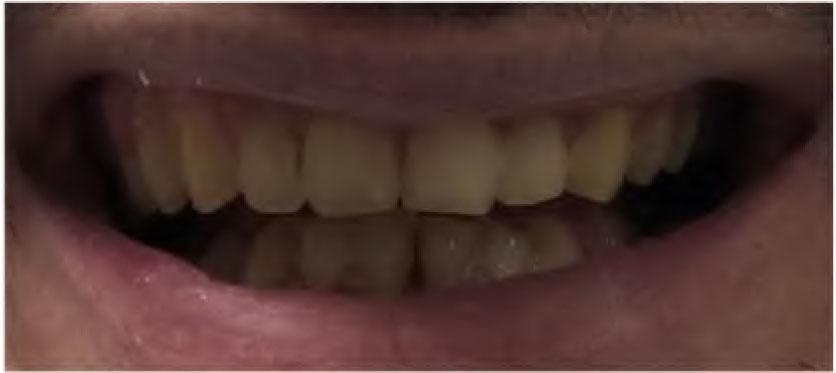

The patient gave written informed consent before the treatment. Fifteen months after the orthodontic treatment (Figure 3), the maxillary incisors were retruded by 2 mm, the mandibular incisors were protruded by 1 mm, leveling of the occlusal plane of the upper and lower dental arch by 0.5mm according to cephalometric analysis. Facial convexity was also reduced with the retraction of upper lip and marked improvement in aesthetics and function was obtained. Although, there was improvement in the anteroposterior dimension with a decreased overjet, the VDO was reduced. The patient was provided with removable vacuum-formed retainers in the maxilla and mandible. The thickness of the retainers was 2 mm. Retainers have been used for 2 months. The patient’s muscle sensitivity and temporomandibular pain were evaluated in this period. No muscle hyperactivity or TMD was found.

Figure 3. Initial preoperative view after the orthodontic treatment